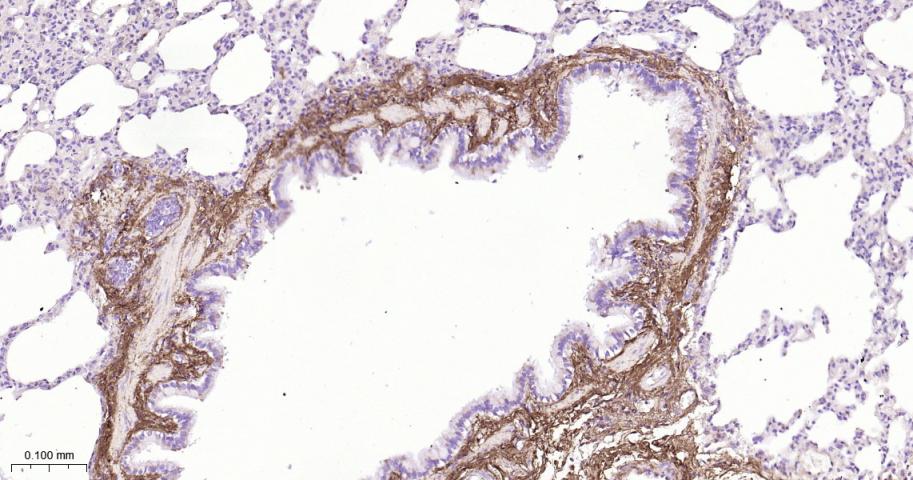

Paraformaldehyde-fixed, paraffin embedded Human Lung; Antigen retrieval by boiling in sodium citrate buffer (pH6.0) for 15 min; The section was incubated with Collagen I Polyclonal Antibody, Unconjugated (bs-10423R) at 1:800 overnight at 4°C, followed by conjugation to the bs-0295G-HRP and DAB (C-0010) staining.

Paraformaldehyde-fixed, paraffin embedded Rat Lung; Antigen retrieval by boiling in sodium citrate buffer (pH6.0) for 15 min; The section was incubated with Collagen I Polyclonal Antibody, Unconjugated (bs-10423R) at 1:800 overnight at 4°C, followed by conjugation to the bs-0295G-HRP and DAB (C-0010) staining.

Paraformaldehyde-fixed, paraffin embedded Mouse Lung; Antigen retrieval by boiling in sodium citrate buffer (pH6.0) for 15 min; The section was incubated with Collagen I Polyclonal Antibody, Unconjugated (bs-10423R) at 1:800 overnight at 4°C, followed by conjugation to the bs-0295G-HRP and DAB (C-0010) staining.